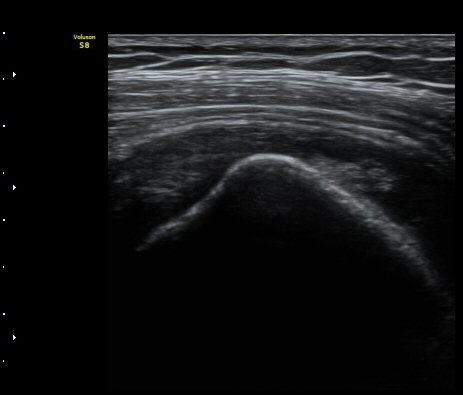

ÃÊÀ½ÆÄ °Ë»ç

¾î±ú À̵ιڱ٠Ⱦ´Ü¸é°Ë»ç¿¡¼­ ½ÉÇÑ Á¡¾×³¶³» ¼ö¾×Àú·ù°¡ °üÂûµÇÁö¸¸ ÆÄ¿öµµÇ÷¯

°Ë»ç¿¡¼­ Ç÷·ùÁõ°¡´Â °üÂûµÇÁö ¾Ê´Â´Ù(±×¸² 1, 2).   À̵ιڱ٠¾Æ·¡ Ⱦ´Ü¸é°Ë»ç¿¡¼­